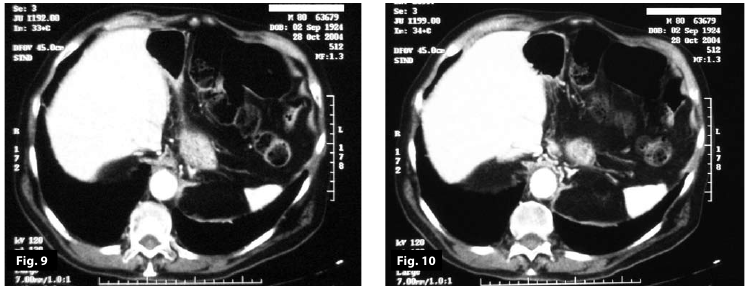

Figure7-8

Figure5-6-7-8